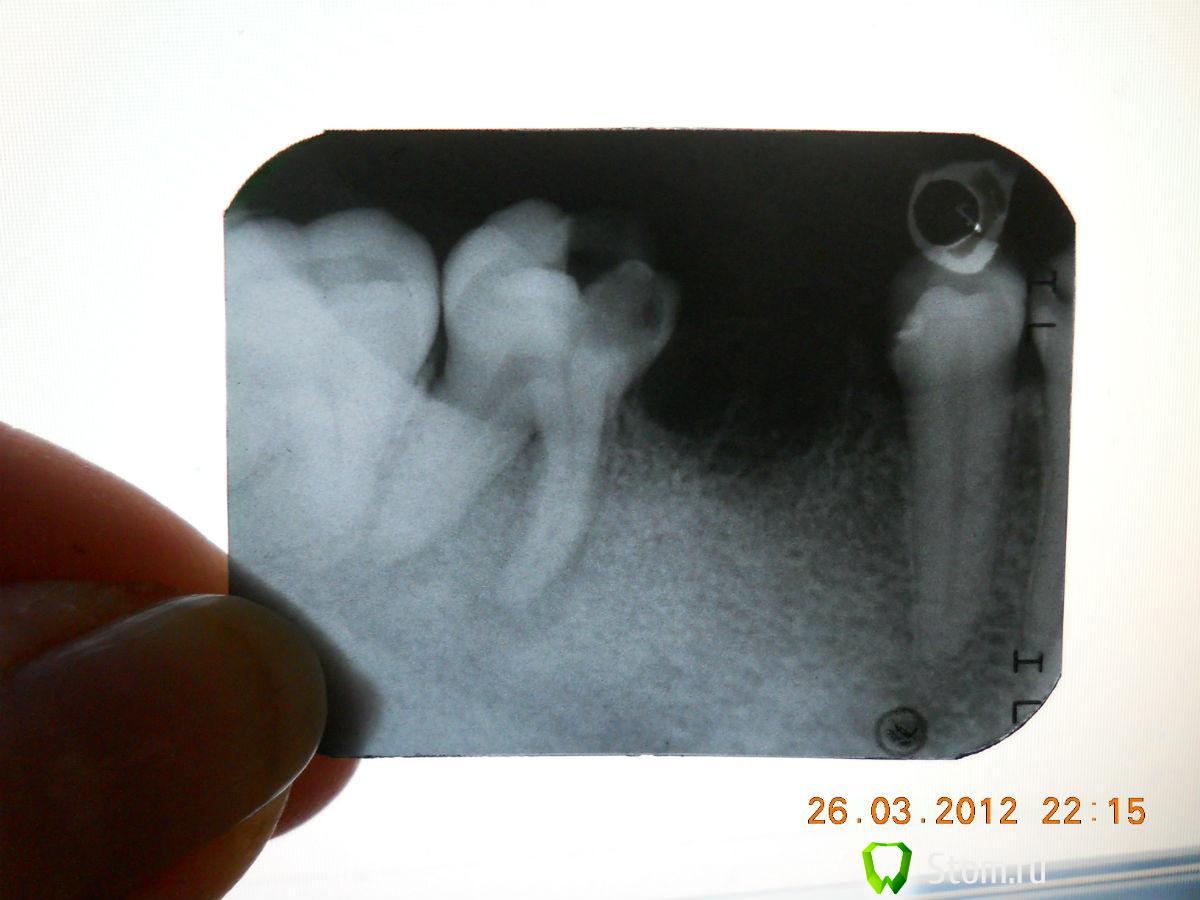

JOY Опубликовано 26 марта, 2012 Поделиться Опубликовано 26 марта, 2012 Добрый вечер уважаемые врачи!Хотелось бы узнать ваше мнение, есть ли шанс что 8 зуб сможет нормально вырасти ..(сейчас он сидит в десне, но чувствуется сквозь нее при нажатии пальцем), 7 зуб у меня удален.Спасибо. Ссылка на комментарий

samsonov Опубликовано 26 марта, 2012 Поделиться Опубликовано 26 марта, 2012 У Вас отсутствует шестой,седьмой- "жестоко" инфицирован.,на 8- кариес.(и он не вырастет нормально) Ссылка на комментарий

JOY Опубликовано 26 марта, 2012 Автор Поделиться Опубликовано 26 марта, 2012 седьмой удалили уже ..то есть 8 мне тоже удалять получается как вылезет или лечить можно? Ссылка на комментарий